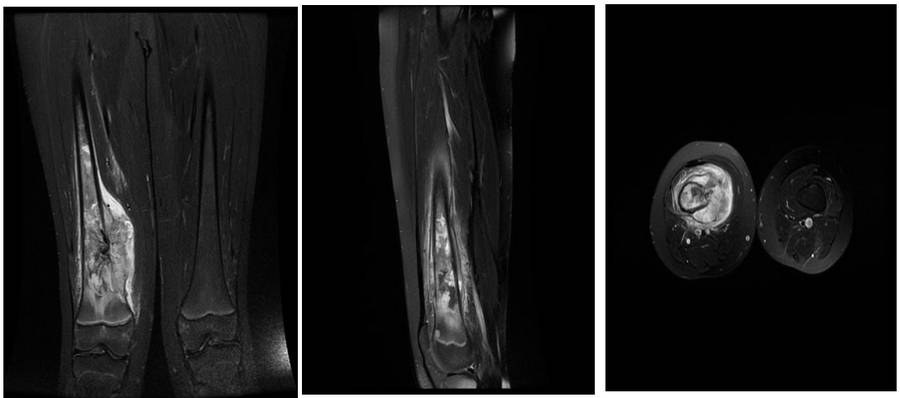

Ameliyat Öncesi: MR’da distal femur medial yerleşimli kemikte harabiyete neden olup yumuşak dokuya uzanan ve ödemin eşlik ettiği tümör dokusu görülmekte